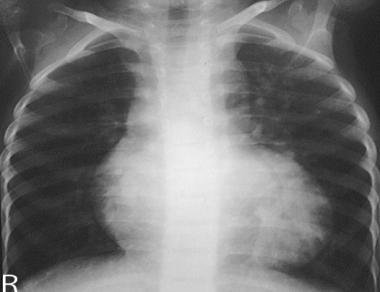

- cardiomegaly - an enlarged heart